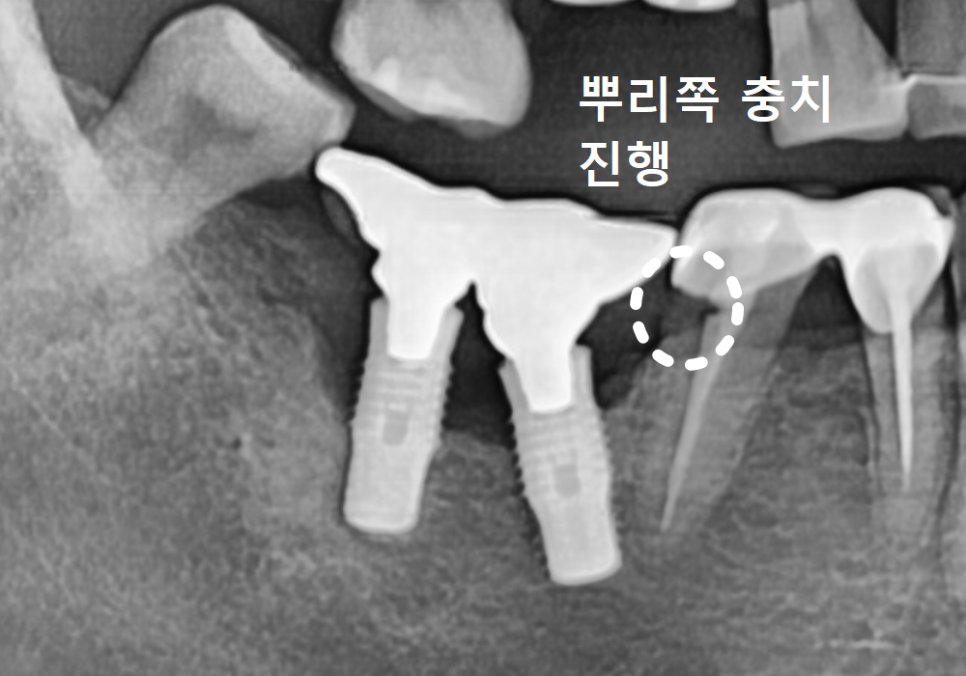

특히 CT로 분석해 보니 임플란트를

양옆에서 꽉 잡아줘야 할 뼈 중

한쪽 면이 염증으로 완전히 소실되어 있었죠.

게다가 뒤쪽에 있는 사랑니까지

염증을 더 악화시키고 있었습니다.

그 틈으로 음식물이 계속 끼어 들어가면서

치아 뿌리 깊숙이 충치가 생긴 상태였어요.

불필요한 뼈이식도 막기 위해

CT를 꼼꼼히 분석했고,

꼭 필요한 부분(#47)에만 뼈이식을

동반해 안전하게 식립을 마쳤습니다.